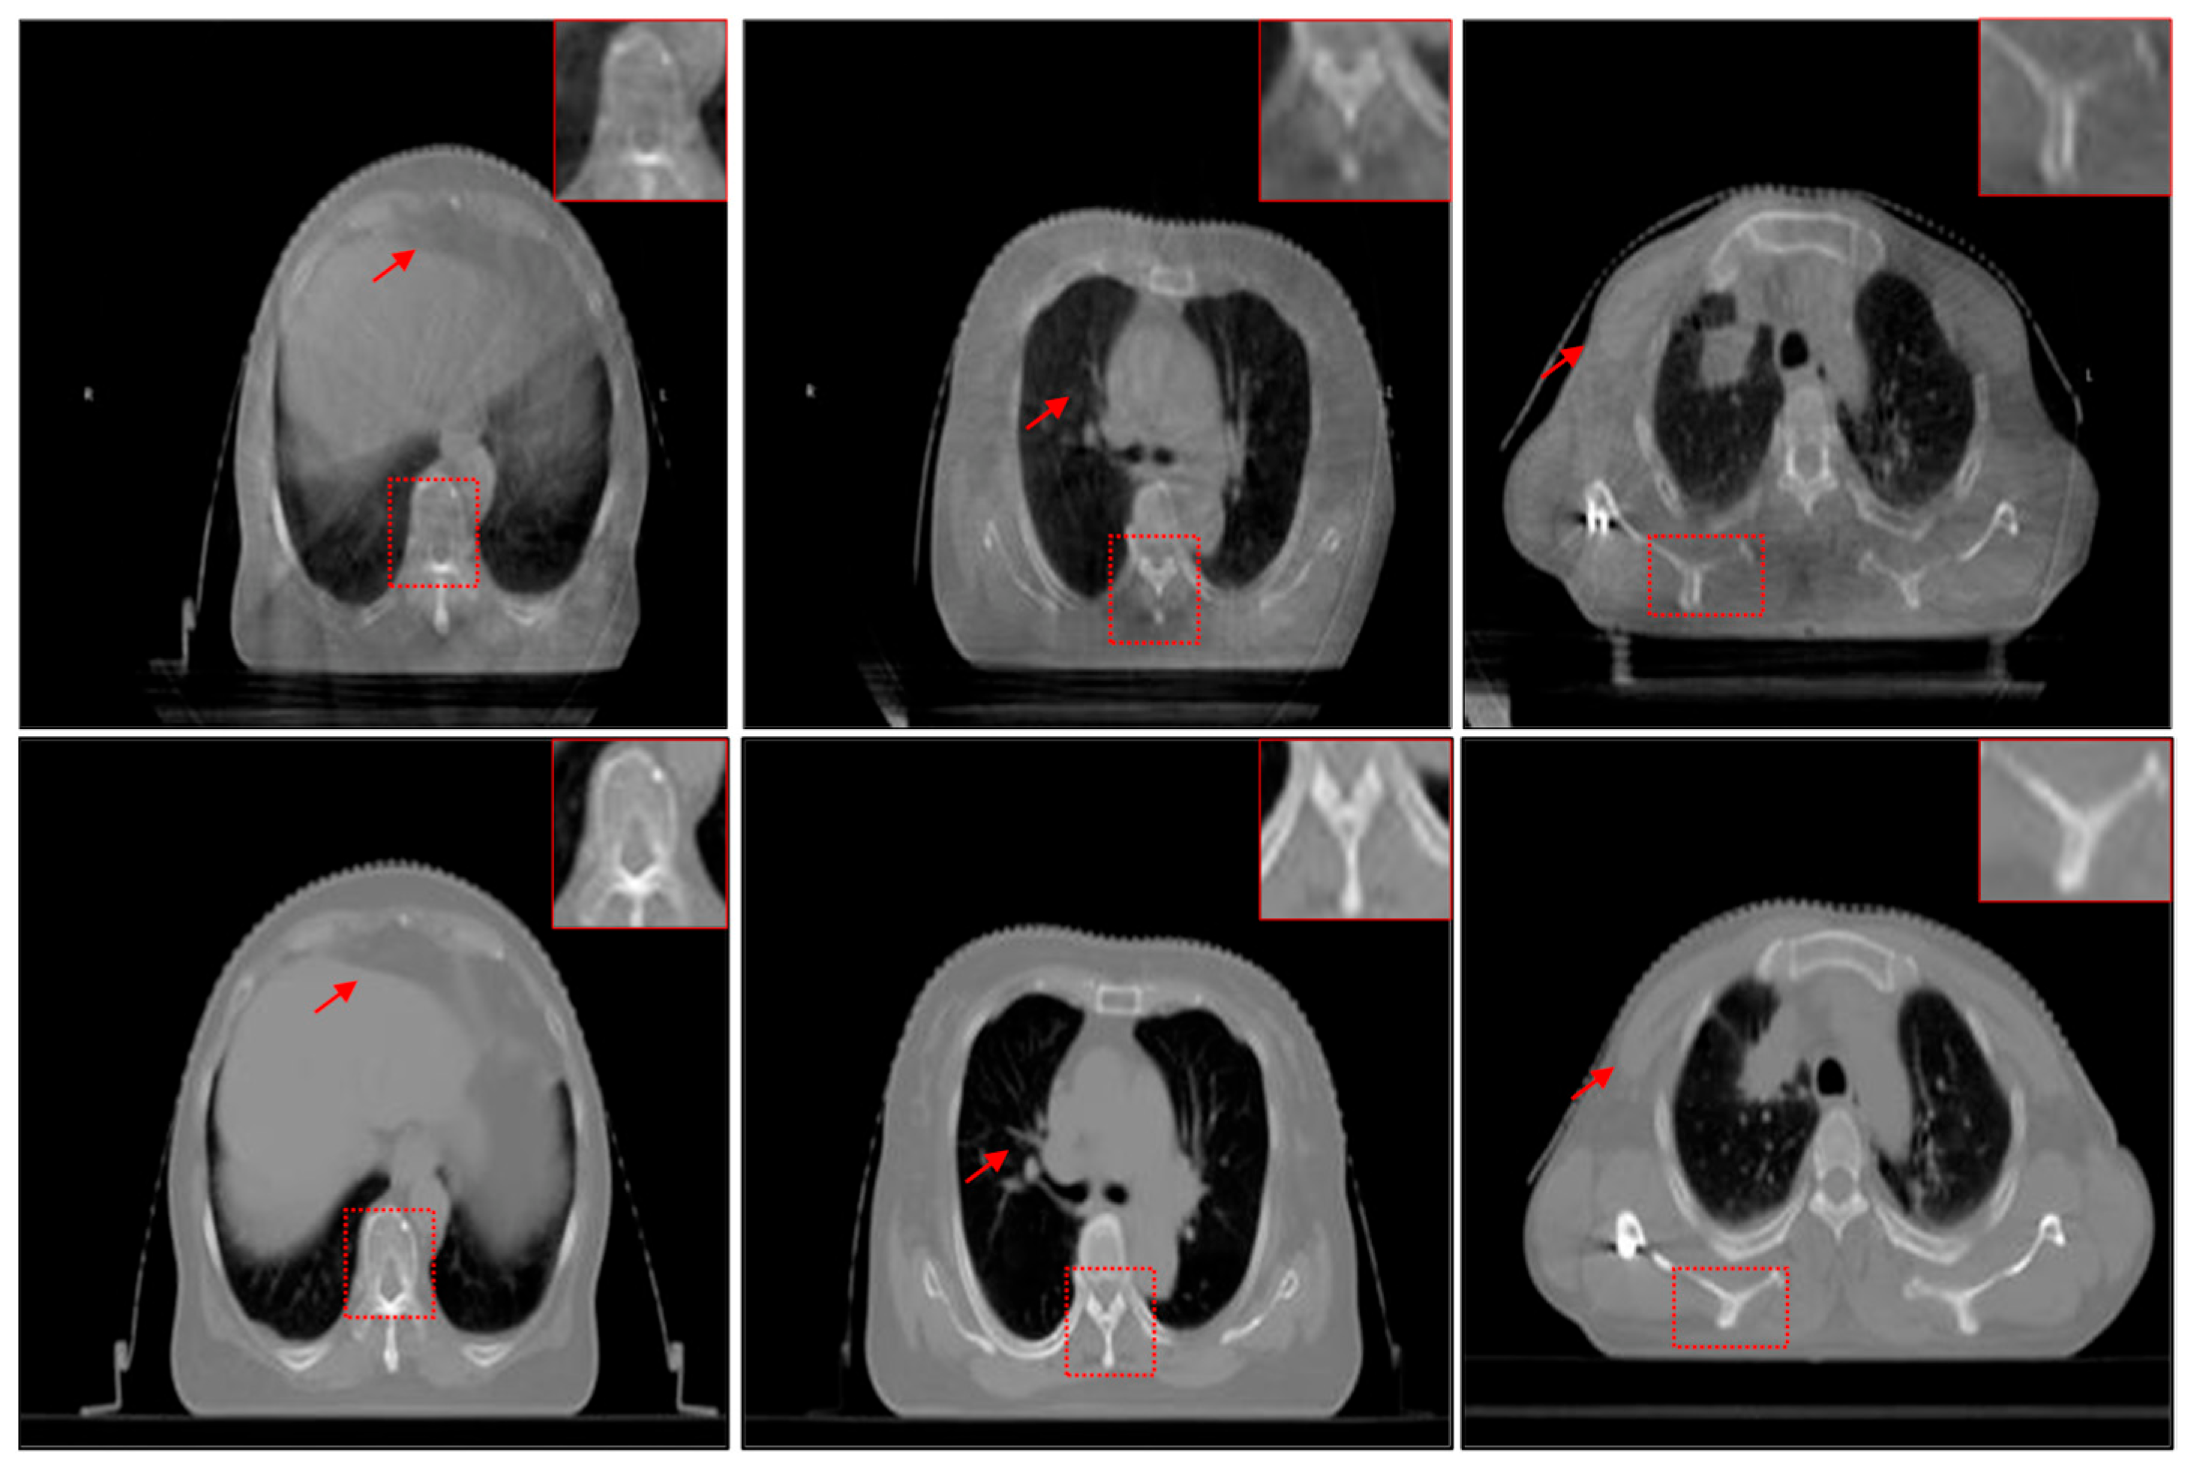

As shown in Figure 1, CBCT images usually have low contrast and visual quality due to their small imaging dose compared with CT images. Compared with CT, CBCT has a small imaging dose, which means that its imaging is more susceptible to interference from environments such as a strong magnetic field, resulting in more noise in the CBCT image. The degradation of CBCT will reduce image contrast and increase the ambiguity of structures of important regions, which makes it unable to play its due role in IGRT [11]. Huang et al. proved that the accuracy of radiotherapy can be improved by using CBCT enhancement technology in IGRT [12]. Thus, it has become a new research topic to use image enhancement technology to improve the quality of CBCT.

Figure 1.

Examples of unregistered CBCT (the first row) and CT (the second row) images.